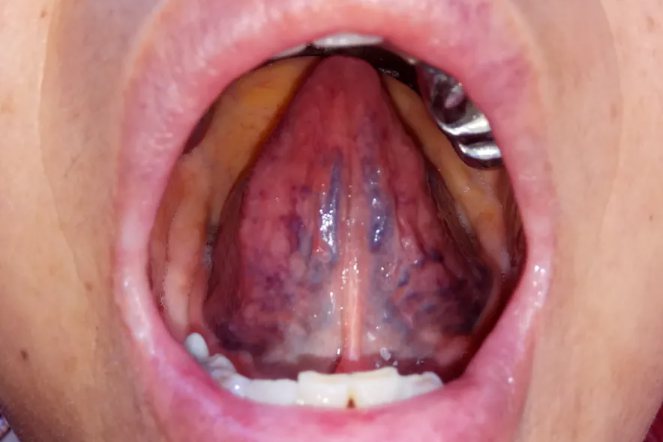

2、舌下络脉

舌下络脉即张口抬起舌头后下方的结构,血瘀时可变粗、曲张,像紫色的珠子一样,大小不等。